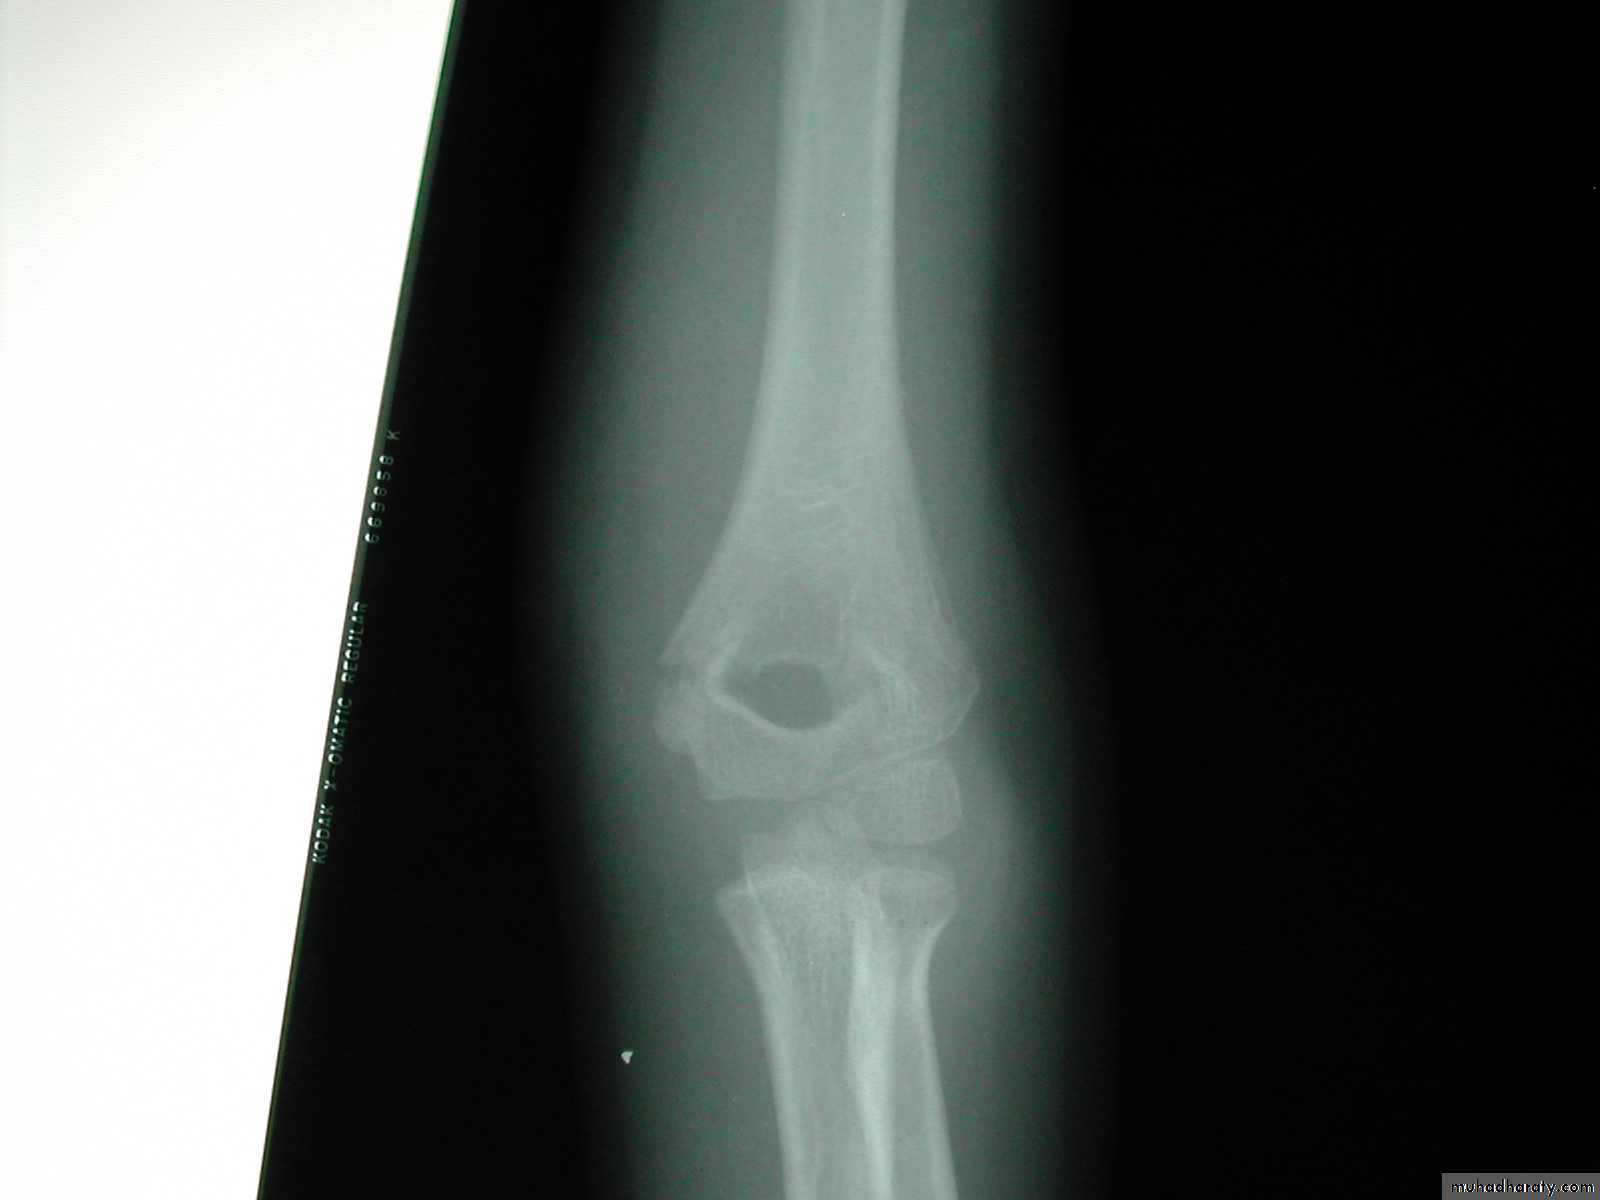

This is how we treated these fractures

when I was a resident !!6 y.o. sustained this FX. NV intact.

Following obtaining a satisfactory closed reduction how do you propose to stabilize it?• Medial-lateral pins

6 y.o. sustained this FX. NV intact.

Following obtaining a satisfactory closed reduction how do you propose to stabilize it?Multiple lateral pins

Outside fracture line ?6 y.o. sustained this FX. NV intact.

Following obtaining a satisfactory closed reduction how do you propose to stabilize it?

Cross pinsantegrade lateral